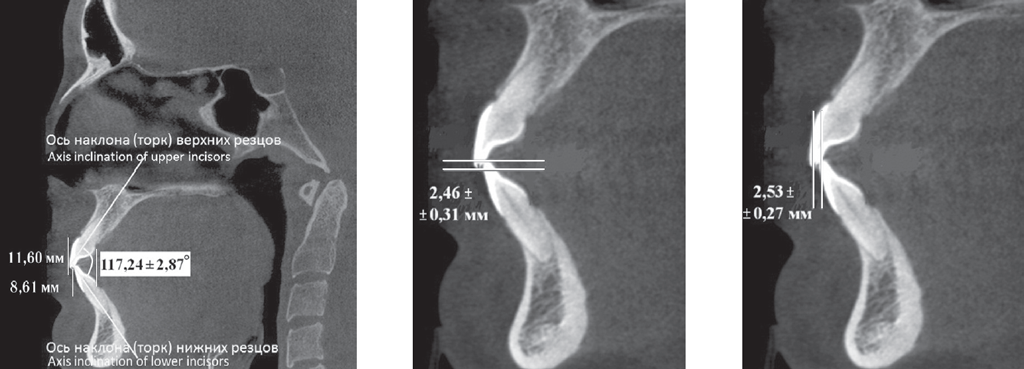

У людей 1-й подгруппы, для которых было характерно протрузионное положение резцов, межрезцовый угол составил 117,24 ± 2,85°. При этом торковые значения верхних резцов по отношению к окклюзионной плоскости составили 12,24 ± 2,48° (рис. 2).

Рис. 2. Физиологическая протрузия резцов на томограммах

Fig. 2. Physiological protrusion of incisors on tomograms

Достоверных отличий при измерении величины перекрытия в сагиттальном и вертикальном направлениях нами не отмечено.

У людей 2-й подгруппы при ретрузии резцов величина межрезцового угла в среднем составила 151,47 ± 2,94°, торк верхних резцов — 5,85 ± 1,42°. При этом величина вертикального перекрытия соответствовала величине сагиттального перекрытия и не превышала 2–3 мм.

У людей 1-й подгруппы, для которых было характерно протрузионное положение резцов, межрезцовый угол составил 117,24 ± 2,85°, при этом торковые значения верхних резцов по отношению к окклюзионной плоскости — 12,24 ± 2,48° (рис. 4).

Рис. 4. Патологическая ретрузия (а) и патологическая протрузия (b)

Fig. 4. Pathological retrusion (a) and pathological protrusion (b)

У пациентов с ретрузией резцов отмечалось увеличение межрезцового угла и уменьшение торковых значений резцов, так же как и при физиологической ретрузии. Однако величина перекрытия существенно отличалась от аналогичных показателей, полученных у пациентов I группы. При этом наблюдалось несоответствие размеров вертикального и сагиттального перекрытия.